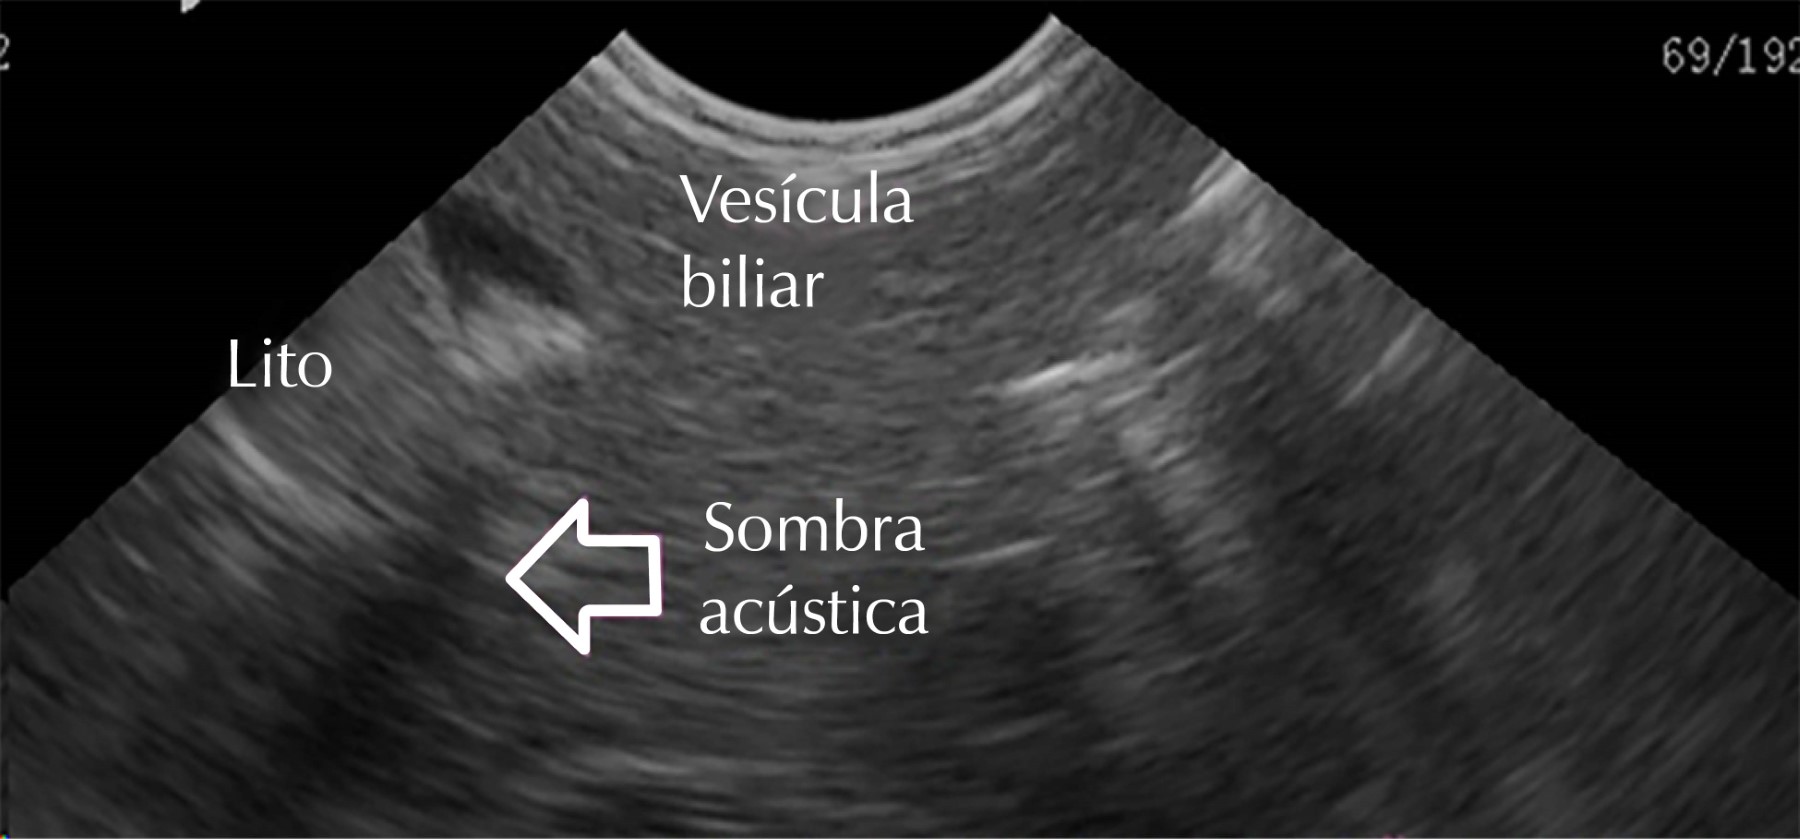

Lactante masculino de un año cuatro meses, quien fue ingresado en un hospital de segundo nivel debido a fiebre y rechazo a la vía oral. El paciente mostraba signos de malestar general e irritabilidad significativa. No tenía antecedentes médicos previos de importancia a esta hospitalización. Al ingreso presentaba fiebre (temperatura de 39.5 °C) y rechazo a la vía oral. Peso 10,500 g, frecuencia cardiaca de 185 por minuto, frecuencia respiratoria (FR) 28 por minuto. Tensión arterial 110.60 mmHg. Se observó irritabilidad y signos de malestar general, pero no se identificaron otros hallazgos clínicos relevantes en la exploración física inicial. Se realizaron pruebas de laboratorio que mostraron una elevación significativa de los marcadores inflamatorios, incluyendo un recuento de leucocitos de 18,000/mm³, con 12% de bandas y una proteína C reactiva (PCR) de 28 mg/dL. El examen general de orina como datos relevantes documentó esterasa leucocitaria ++, PH 5, en el sedimento 130 leucocitos por campo, se diagnosticó al paciente con bacteriemia secundaria a una infección urinaria severa. Los resultados de los cultivos de sangre y orina confirmaron la presencia de Escherichia coli como el agente causal. El paciente recibió tratamiento con ceftriaxona parenteral (100 mg/kg/día) con el objetivo de abordar la bacteriemia y la infección urinaria, 48 horas después de su ingreso, se realizó un ultrasonido renal complementario, el cual reveló la presencia de pseudolitiasis biliar en el área vesicular del paciente (Figuras 2 y 3), por lo que se cambió por amikacina 22 mg/kg/día. Cinco días después fue egresada por mejoría, con seguimiento en la consulta externa. A manera de seguimiento nueve semanas después, se realizó un ultrasonido de control que mostró una vesícula biliar normal, indicando una resolución completa de la pseudolitiasis biliar (Figura 4).

El diagnóstico de la pseudolitiasis biliar se sospecha en pacientes que reciben ceftriaxona y presentan hallazgos ecográficos compatibles, como la presencia de lodo biliar en la vesícula biliar. En un estudio observacional prospectivo en 118 niños hospitalizados tratados con ceftriaxona en los que se realizaron ultrasonidos seriados, 17% presentó anormalidades ecográficas incluyendo lodo biliar y pseudolitiasis.4 Por lo tanto, el ultrasonido abdominal es la herramienta diagnóstica de elección para detectar esta complicación, siendo una técnica no invasiva y ampliamente disponible en la práctica clínica pediátrica.

El diagnóstico se basa en hallazgos ecográficos característicos, lo que subraya la importancia de la capacitación adecuada de los profesionales de la salud para su detección oportuna. Además, es esencial considerar medidas preventivas, como la administración lenta y diluida de ceftriaxona, para reducir el riesgo de su desarrollo.